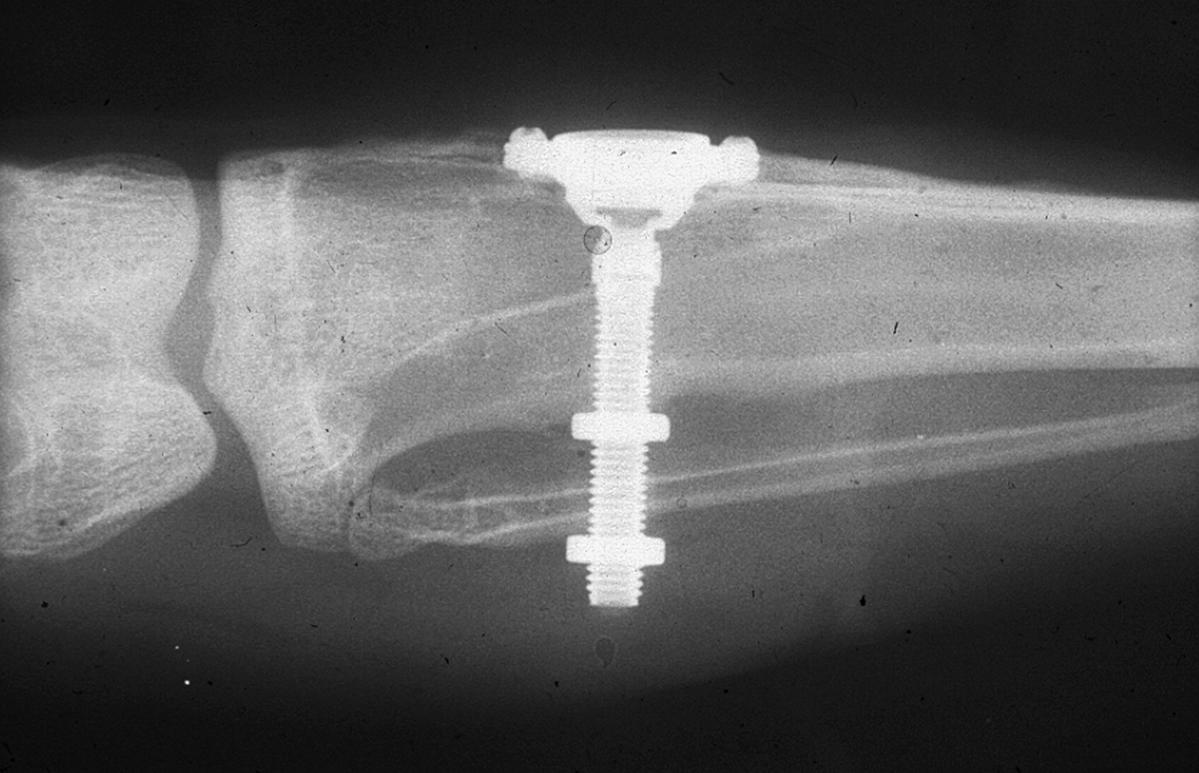

Branemark’s_initial_radiograph